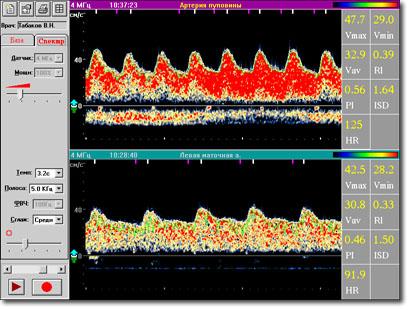

Суть метода состоит в изучении спектральных характеристик допплеровского сигнала при непосредственной локации сонных артерий. Получаемая в реальном масштабе времени спектрограмма состоит из точек разного цвета, совокупность которых дает спектр скоростей в поперечном сечении артерии за время сердечного цикла. Положение данной точки по отношению к оси ординат (шкала частот) соответствует определенной линейной скорости кровотока (выражаемой в соответствии с принципом Допплера в КГц), а ее цвет - удельному весу данной частоты в спектре (при максимальной интенсивности точка окрашивается в красный, при минимальной - в синий цвета).